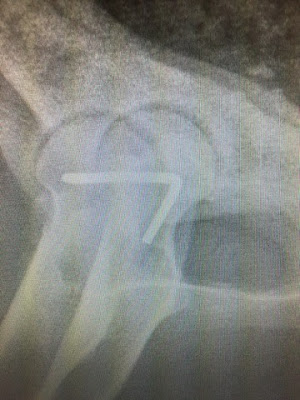

Røntgen av Chena sin hofte med innsatt splint etter operasjon (AniCura Dyresykehuset i Tromsø).

Men så skjedde det som ikke skulle skje. Ni dager etter ulykken gikk hofta ut av ledd på nytt. Fryktelig smertefult for stakkars Chena som igjen måtte rett til veterinær - med blålys! Takk og lov for at vi har flinke, erfarne kirurger her i byen! Veterinær Bente Akselsen ved AniCura Dyresykehuset i Tromsø tok godt imot oss og opererte Chena samme formiddag. Chena fikk satt inn en splint i hofteleddet som skal stabilisere / holde leddet på plass.